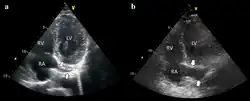

Exemplo de ECG do dispositivo a) flutuando livremente no VD b) em contato com a parede do VD

Exemplo de ECG do dispositivo a) flutuando livremente no VD b) em contato com a parede do VD -

É possível colocar o eletrodo no seio coronário, normal (esquerdo) dilatado (direito). Tal colocação é aceitável.

É possível colocar o eletrodo no seio coronário, normal (esquerdo) dilatado (direito). Tal colocação é aceitável.